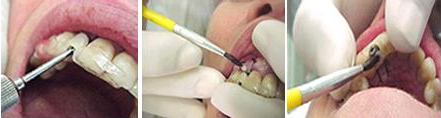

Figura 1A. Esta é a região onde serão realizados os implantes.

Inicialmente foi realizada uma ampla profilaxia na cavidade bucal do paciente, com aplicação do jato de bicarbonato e nos lugares onde havia cálculo esses foram removidos com o ultra-som.

Figura 1B, com o alta rotação e uma broca diamantada foi removido o macho de encaixe do attachement, para a colocação dos implantes de das coroas imediatas na posição correta.

Figuras 5 A e B.

A primeira mostra o guia cirúrgico em posição com o paciente anestesiado e em situação correta para serem marcados os dois pontos para a perfuração. Inicialmente os pontos foram marcados no tecido mole, em seguida, figura 5 B, o tecido ósseo subjacente foi marcado com a primeira broca, broca chama. Essa marca em nada prejudica, pois, a incisão, inicial, quando a coroa vai ser colocada de imediato é diferente das incisões onde os implantes devem permanecerem sepultados por 3 ou 6 meses.

As incisões, para a colocação dos implantes Conect, com coroas imediatas são diferentes das incisões quando os implantes devem permanecer sepultados.

Figura 6. Nesta fotografia vemos as duas cavidades prontas para receberem os implantes Conect. Foram usadas as seguintes brocas: Chama, 2,8mm, 3,0mm e a broca do Kit Conect da broca de 4,3 – 11,5mm, para colocação do implante correspondente deste diâmetro e comprimento.

Figura 7. Nesta fotografia vemos o implante na área do 36, colocado com o motor de implante, usando-se 1250rpm e com um contra-ângulo de 1:256, o que segundo o fabricante oferece um torque de até 32N. Depois deste procedimento usa-se uma chave, que levará o implante até sua ancoragem final, tendo-se para isso que retirar o monta implante e fazer esta inserção final com um intermediário próprio, o que já havia sido realizado. Em seguida, novamente o monta implante é recolocado, implante 36 e depois no 37 para se fazer a transferência do similar para o modelo como veremos.